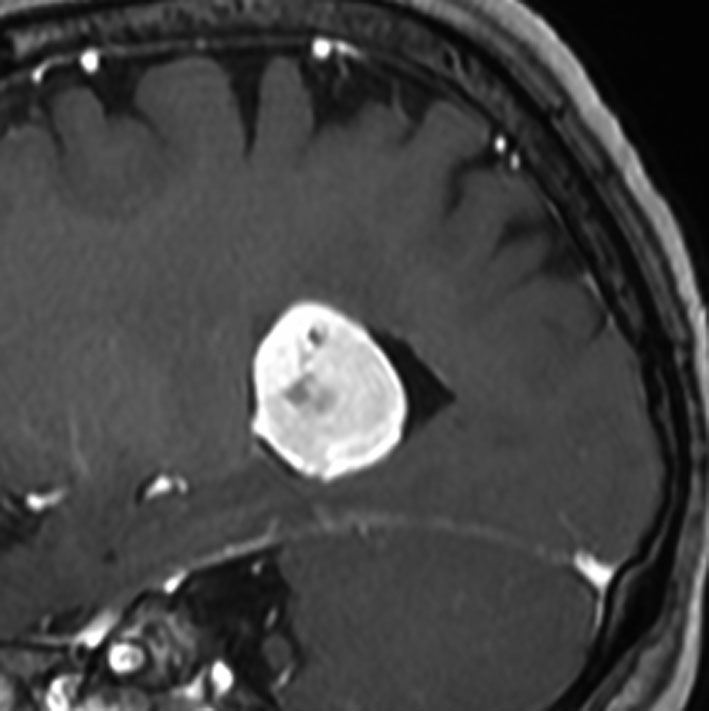

側脳室三角部髄膜腫 lateral ventricle (trigon) meningioma

50歳くらいの女性に偶然発見された三角部髄膜腫です。この部位はとても巨大にならないと症状が出ないので,しばらく様子を見ることにしました。

5年後です。増大傾向が止まりません。大きくなると手術リスクがすごく高くなるので,開頭手術で摘出することにしました。

右側は,手術翌日のMRIです。頭頂部の皮質経由で腫瘍は全摘出できています。専門的には,頭頂部経皮質到達法 parietal transcortical approach, high-parietal approachといいます。この患者さんは幸い頭頂葉症状は全く出ませんでした。でも巨大な三角部髄膜腫になると頭頂葉症候が手術後遺症として残ることがあります。でも慎重な手術をすれば日常生活に大きな支障となることはほとんどないでしょう。